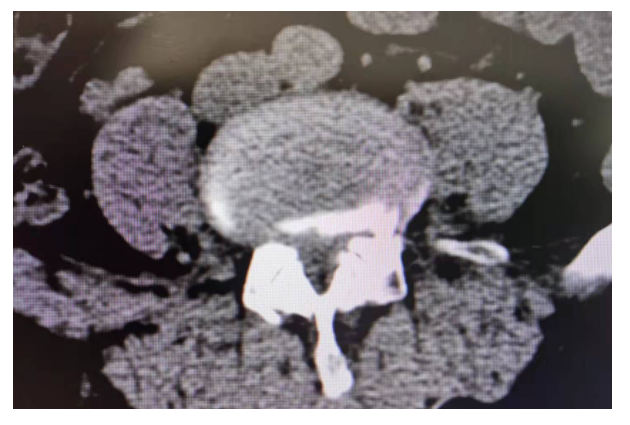

主诉:腰部疼痛3年,加重伴双下肢疼痛麻木1年

现病史:3年前出现腰部疼痛、酸困,无下肢疼痛麻木不适,弯腰活动受限,行走及站立时疼痛加重,平卧休息稍减轻,未治疗,上述症状持续加重,近1年来又出现双下肢疼痛麻木,以左侧为著,步行困难,步行能力约100米,为求诊治,现来我院,遂以“腰椎管狭窄症”为诊断收住我科。发病以来,饮食正常,睡眠一般,体力正常,大小便正常。